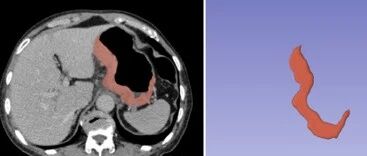

基于深度学习的早期急性胰腺炎严重程度分级预测 放射学实践 · 公众号 · 医学 · 9 月前 · |